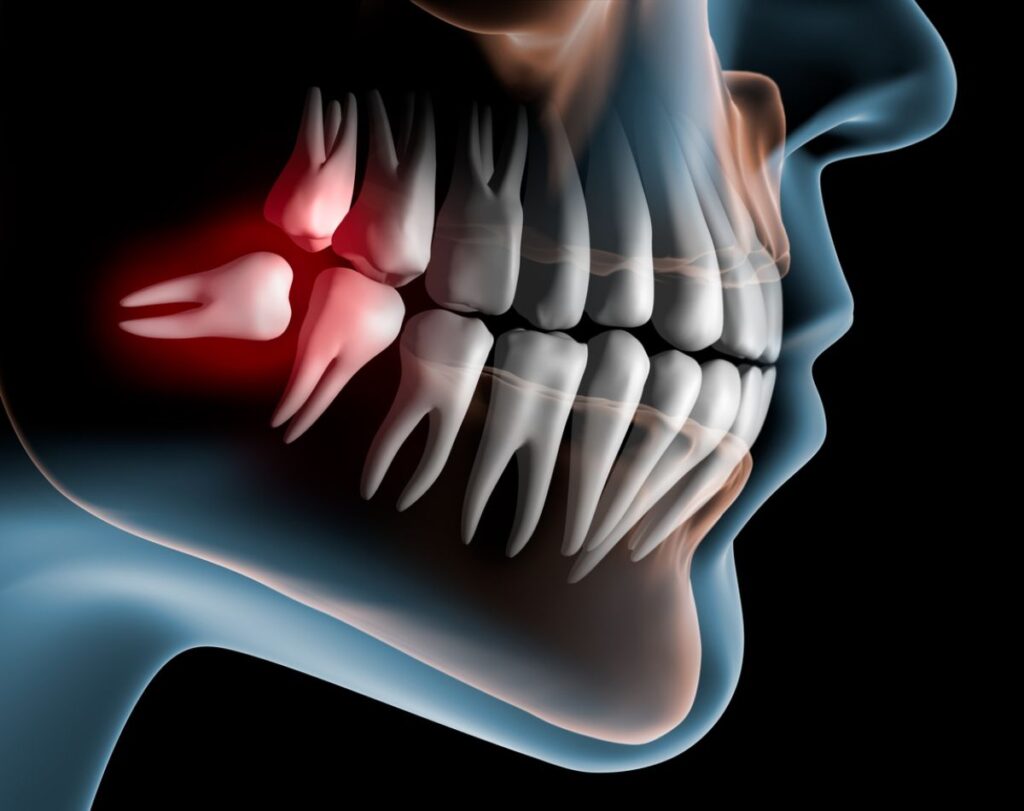

Wisdom teeth are the last set of teeth to erupt in the oral cavity, typically between the ages of 17 and 25, and are located at the back of the upper and lower jaws. However, some people may not develop wisdom teeth until their 40s or 50s. If the wisdom teeth fail to erupt, they need to be extracted. At Radiant Maxillofacial Surgical Centre and Dental Clinic, we offer various types of wisdom teeth extractions.

While all four wisdom teeth may naturally erupt without causing any issues, many people experience problems when the teeth erupt at an angle or remain partially or entirely impacted below the gum line or in the jawbone. Some of the issues that can arise include:

- Food lodgement leading to bacterial growth and tooth decay

- Gum and jaw problems, such as infection and swelling

- Crowding and malocclusion, which can affect the appearance of the teeth